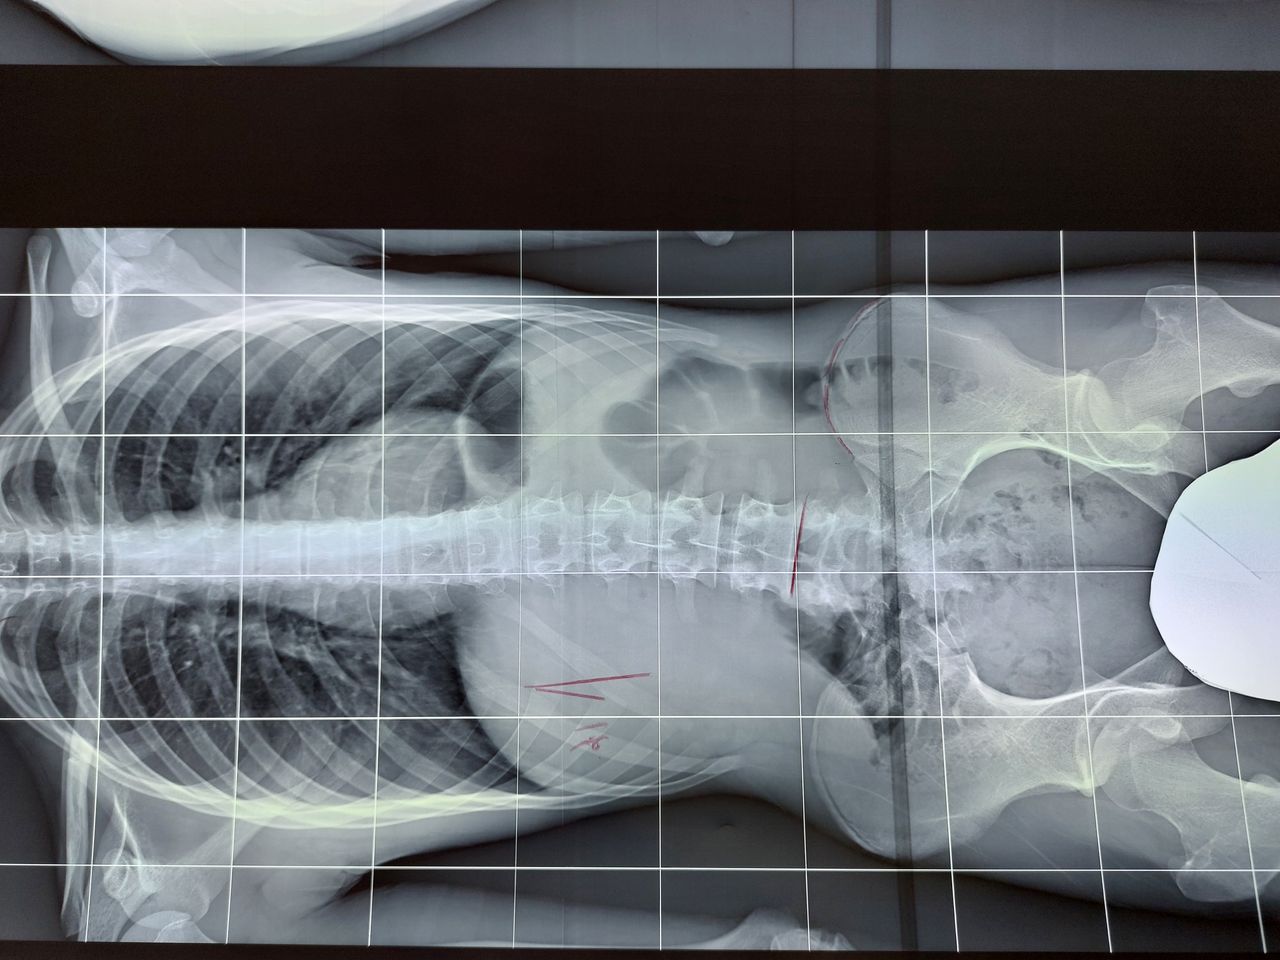

Salve buona sera gentili spettabili dottori l'anno scorso mi trovavo al pronto soccorso scrivo da Sanremo Liguria e dopo lastre e venuto fuori che avevo una frattura al coccige a novembre del anno scorso . Ma in sentivo dolori e la cosa strana e che io non ero caduta una caduta lebbi 5 anni fa dalle scale ma era risultato che avevo solo le costole rotte e niente altro ma già dal 2019 dopo la caduta cominciai a soffrire di solito di schiena forti a ogni sforzo di servizio fisico lavorativo e questi dolori si accentuavano di più anche una settimana arriva del ciclo e anche durante il ciclo Poi mi avevano fatto pure una lastra alla schiena ed era venuto fuori una discopatia alla schiena ma non si sa di che tipo di discopatia. Ora però l'anno scorso era un anno più o meno che non avevo più dolori forti ma erano diminuiti alla schiena in questi ultimi mesi di quest'anno sarà per errore che non avendo cose morbide per potermi sedere soprattutto quando vado in bagno perché non lavora attualmente per altri problemi di salute. E non ho entrate economiche. Ma fatto sta che adesso sarà un mese che ho di nuovo il coccige che mi fa male che non riesco a sedermi e la schiena è aumentato il dolore a cui ho difficoltà ad abbassarmi a sedermi e anche per dormire chiedo consigli cosa mi conviene fare per potermi riprendere e che attività potrai ancora svolgere in questo stato anche se poi ho anche problemi alla schiena discopatia e anche al ginocchio gonartrosi bilaterale infiammazzione e riduzione cartilagine del ginocchio sinistro Ringrazio cordialmente i spettabili dottore attendo un vostro riscontro buona sera.

gentile signora . di solito succede che il corpo, a seguito di cadute, corregge il tiro con accomodamenti posturali. nel tempo pero' arriva sempre il conguaglio di tutto cio' che abbiamo accumulato come patologie. lei è stata specifica e meriterebbe una risposta specifica, ma bisogna fare i conti con la realtà. dovrebbe andare da un collega il quale sarebbe in grado di aiutarla ma se no puo' si accontenti di piccoli accorgimenti. tutta la colonna è un sistema e adesso il sistema è in tilt. bisogna che lei si metta in posizione supina con le gambe flesse e fare delle respirazioni diaframmatiche se il dolore è urente, muovere entrambi le gambe flesse a destra e sinistra completamente per muovere il bacino e sacro. mettersi un lato , e anche dall'altro successivamente, in modo comodo tale da mettere un arto dritto e l'altro, non a contatto con il letto o lettino , allungato . compiere respirazioni e sentire dove fa male e aspettare il rilassamento. di piu' al momento non posso dirle. appena puo' vada da un Osteopata e quando si siede metta una ciambella.